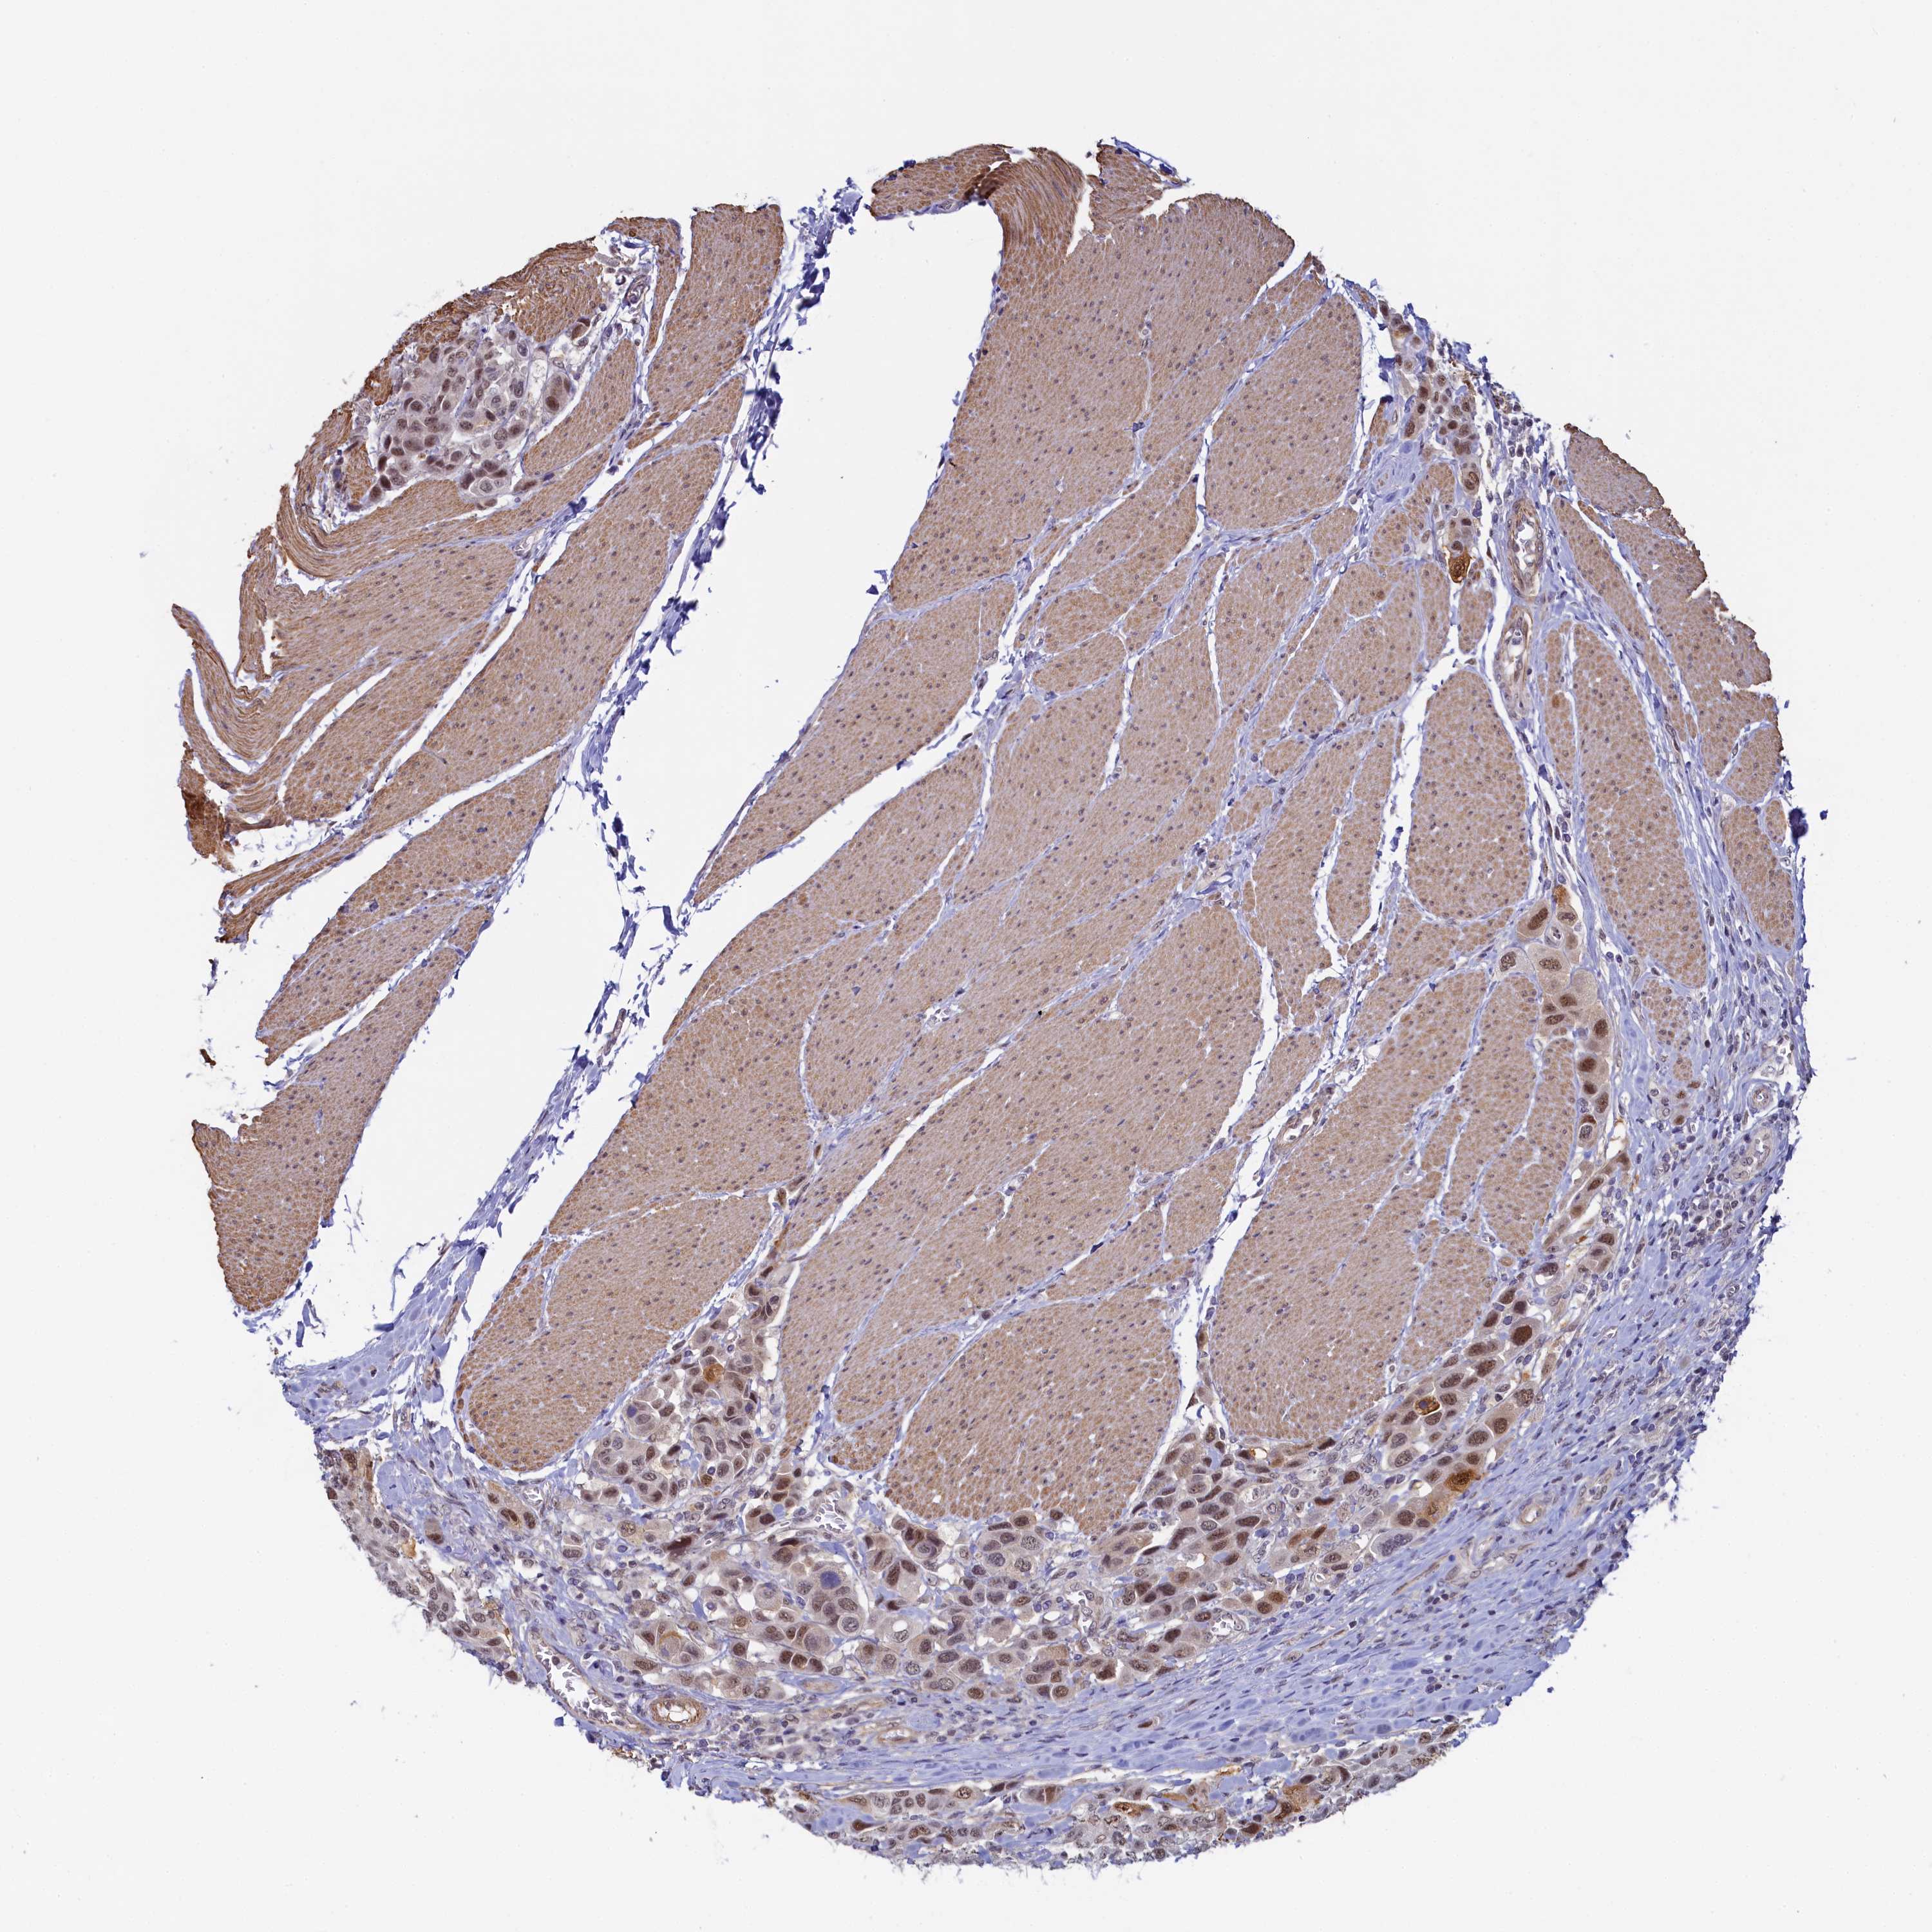

UROTHELIAL CANCER - Protein expressioni

A mouse-over function shows sample information and annotation data. Click on an image to view it in a full screen mode. Samples can be filtered based on level of antibody staining by selecting one or several of the following categories: high, medium, low and not detected. The assay and annotation is described here.

Note that samples used for immunohistochemistry by the Human Protein Atlas do not correspond to samples in the TCGA dataset.

Antibody stainingi

Antibody staining in the annotated cell types in the current human tissue is reported as not detected, low, medium, or high, based on conventional immunohistochemistry profiling in selected tissues. This score is based on the combination of the staining intensity and fraction of stained cells.

Each image is clickable and will lead to virtual microscopy that enables deeper exploration of all samples and also displays staining intensity scores, fraction scores and subcellular localization as well as patient and tissue information for each sample.

Antibody HPA040255

Antibody HPA040651

Urothelial carcinoma, High grade

Urothelial carcinoma, Low grade